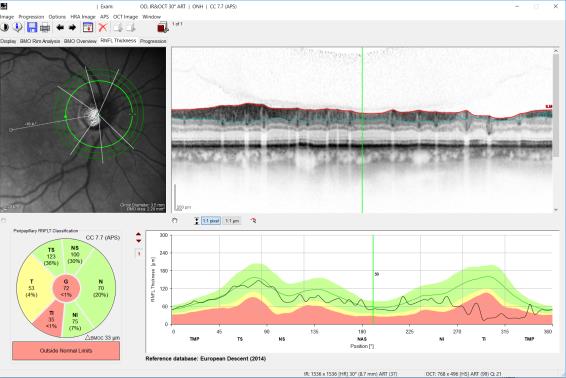

Οπτική τομογραφία (OCT)

H OCT αποτελεί ό,τι πιο μοντέρνο και ακριβές υπάρχει στην οφθαλμολογία στον τομέα της διαγνωστικής του γλαυκώματος. Χάρις στην εξέταση αυτή γίνονται ανιχνεύσιμες μικροαλλαγές σε κυτταρικό επίπεδο, που καθιστούν δυνατή τη διάγνωση του γλαυκώματος στα πολύ αρχικά του στάδια, όταν ακόμα αυτό δεν είναι εφικτό από τον οφθαλμίατρο (με βάση την κλινική εξέταση και τις λοιπές διαγνωστικές εξετάσεις) και φυσικά πολύ προτού ο ασθενής έχει τα πρώτα συμπτώματα/δυσκολίες. Πιο συγκεκριμένα, με την OCT διενεργείται η μέτρηση του πάχους των νευρικών ινών (RNFL) γύρω από την κεφαλή του οπτικού νεύρου καθώς και του πάχους των γαγγλιακών κυττάρων (GCL) στην ωχρά κηλίδα με καταπληκτική ακρίβεια. Με τον τρόπο αυτό γίνονται ανιχνεύσιμες πολύ πρώιμες αλλοιώσεις (δηλαδή μειώσεις του πάχους της RNFL ή/και της GCL). Αυτό έχει ιδιαίτερη σημασία για την πρόγνωση της νόσου, διότι όσο πιο νωρίς γίνει η διάγνωση του γλαυκώματος και όσο επομένως πιο πρώιμα μπει ο ασθενής σε πρόγραμμα στενότερης παρακολούθησης και κατάλληλης θεραπείας, τόσο ευνοϊκότερη είναι η τελική έκβαση της νόσου.

OCT σε υγιές οπτικό νεύρο

OCΤ σε γλαυκωματικό ασθενή